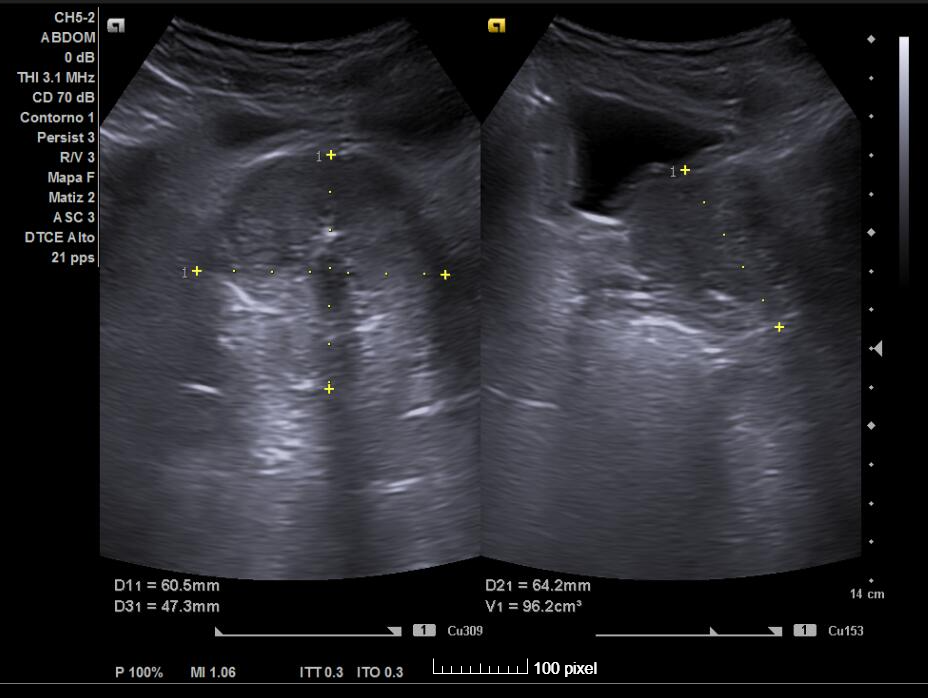

Estuvo en seguimiento por Urología con motivo de litiasis renales izquierdas no obstructivas que se trataron con litotricia extracorpórea e hidronefrosis derecha grado 2-3 secundaria a litiasis ureteral derecha y litiasis vesicales. Además, en esa última visita hace un año se diagnosticó de Hiperplasia benigna de próstata (con volumen prostático de 78 cc) pautando Urología Dutasterida, Tamsulosina y Serenoa repens, descartando otras patologías nefrourológicas.

Acude a consulta de primaria por presentar aumento de urgencia miccional y nicturia habitual desde hace unos meses pese a tratamiento indicado por parte de Urología. Presentando asimismo microhematuria en anormales y sedimentos de orina.

Por este motivo se solicita ecografía clínica para valorar la vía urinaria.

Ecografía clínica urinaria:

Diagnóstico: ureterectasia con ureteroceles bilaterales.